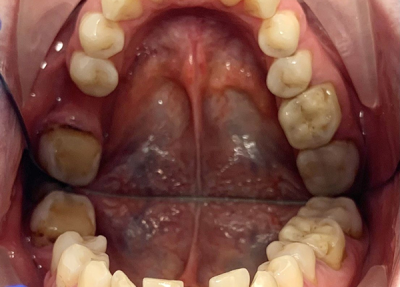

Пациент (30 лет), адентия 46 зуба, 36 периодонтит.

Установлено 2 импланта, 36 с одномоментной имплантацией в лунку удаленного зуба.

Проведена коррекция десневого контура (ССТ с бугра верхней челюсти).